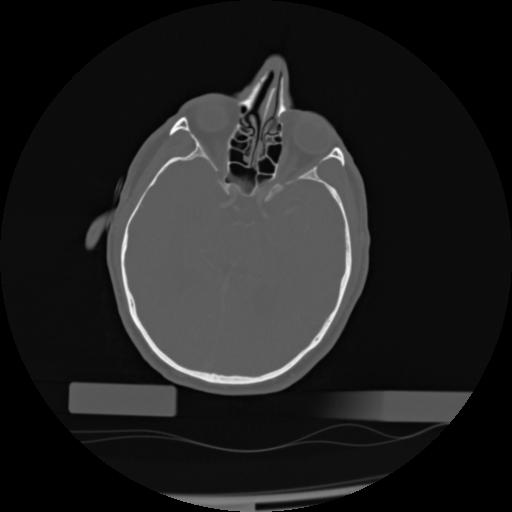

21 ANGIO,CE,Axial,3.0,ANGIO,,